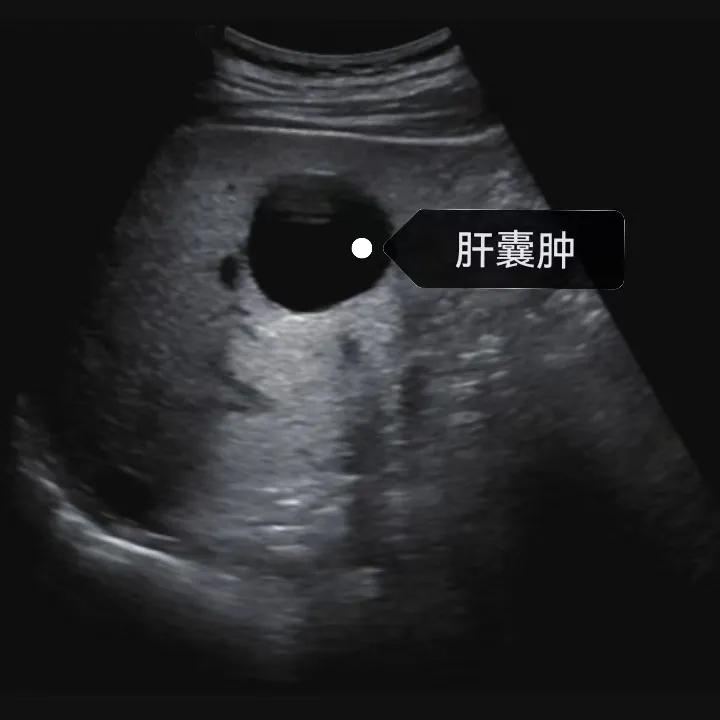

漯河市中醫(yī)院健康科普:認(rèn)識(shí)肝囊腫

肝囊腫是一種常見的肝臟良性疾病,呈圓形或橢圓形,外由上皮細(xì)胞包裹形成包膜,內(nèi)由清亮、無色、無細(xì)胞成分的囊液填充,看上去就像是一顆注滿了水的氣球,因此通俗一點(diǎn)說就是肝臟中的“水泡”。

超聲通常是診斷肝囊腫的首選方法,彩超對(duì)肝囊腫的檢出率可達(dá)98%,<1cm的囊腫也可檢出。肝囊腫常表現(xiàn)為圓形或橢圓形無回聲,包膜光滑完整,邊界清晰,可有側(cè)壁回聲失落征象,后方回聲增強(qiáng)。病程長、囊腫較大者或囊內(nèi)有過出血、感染者,無回聲腔內(nèi)可見少量絮狀回聲漂浮。超聲對(duì)肝囊腫的診斷準(zhǔn)確而靈敏,且方法簡(jiǎn)單、無創(chuàng)、費(fèi)用低、可重復(fù)性高,因此常常被作為首選。